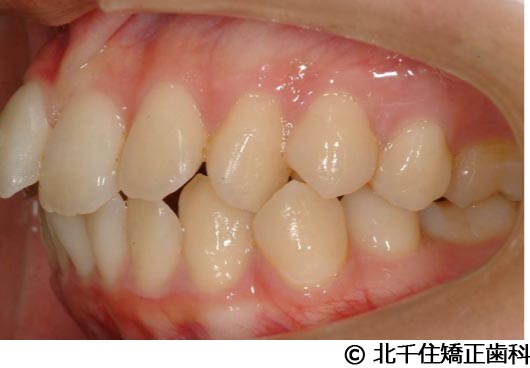

【症例4】下顎前突

- 治療前

- 治療後

- 治療名

- 下顎前突

- 費用

- 1,226,000円(税込)

- 期間

- 2年10ヵ月

- 治療回数

- 32回

- 通院頻度

- 1ヵ月ごと

- 年齢・性別

- 28歳5ヵ月・女性(初診時)

治療内容

-

患者様の症状

主訴:デコボコ、笑顔のとき歯がきれいに見えるようにしたい

治療方法

骨格性の下顎前突および開咬、上顎第二小臼歯と下顎第一小臼歯4本抜歯してワイヤー矯正(セラミックブラケット)。

治療結果

骨格性下顎前突および開咬に対し、抜歯を併用した矯正治療により歯列および咬合関係の調整を行った症例である。治療後は保定装置を使用し、歯列および咬合の安定維持を目的として定期的な経過観察を行っている。

※治療結果は個人差があります。

治療を行う上での注意点(リスク・副作用)

歯磨き不良に伴うカリエスや歯周病、歯根吸収など。